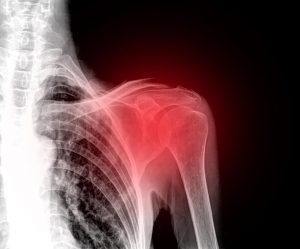

Skuldersmerter er en meget ubehagelig og invaliderende tilstand, fordi skulderleddet giver dig mulighed for at interagere effektivt med dit miljø. Der er forskellige typer af skader, der kan forårsage smerte, hævelse og immobilitet. Du kan også opleve kronisk hævelse, hvis du ikke modtager nogen medicinsk behandling.

Skuldersmerter er mere almindeligt, end du tror. Tal med din læge, hvis du har mistanke om skade, så det kan blive behandlet korrekt.